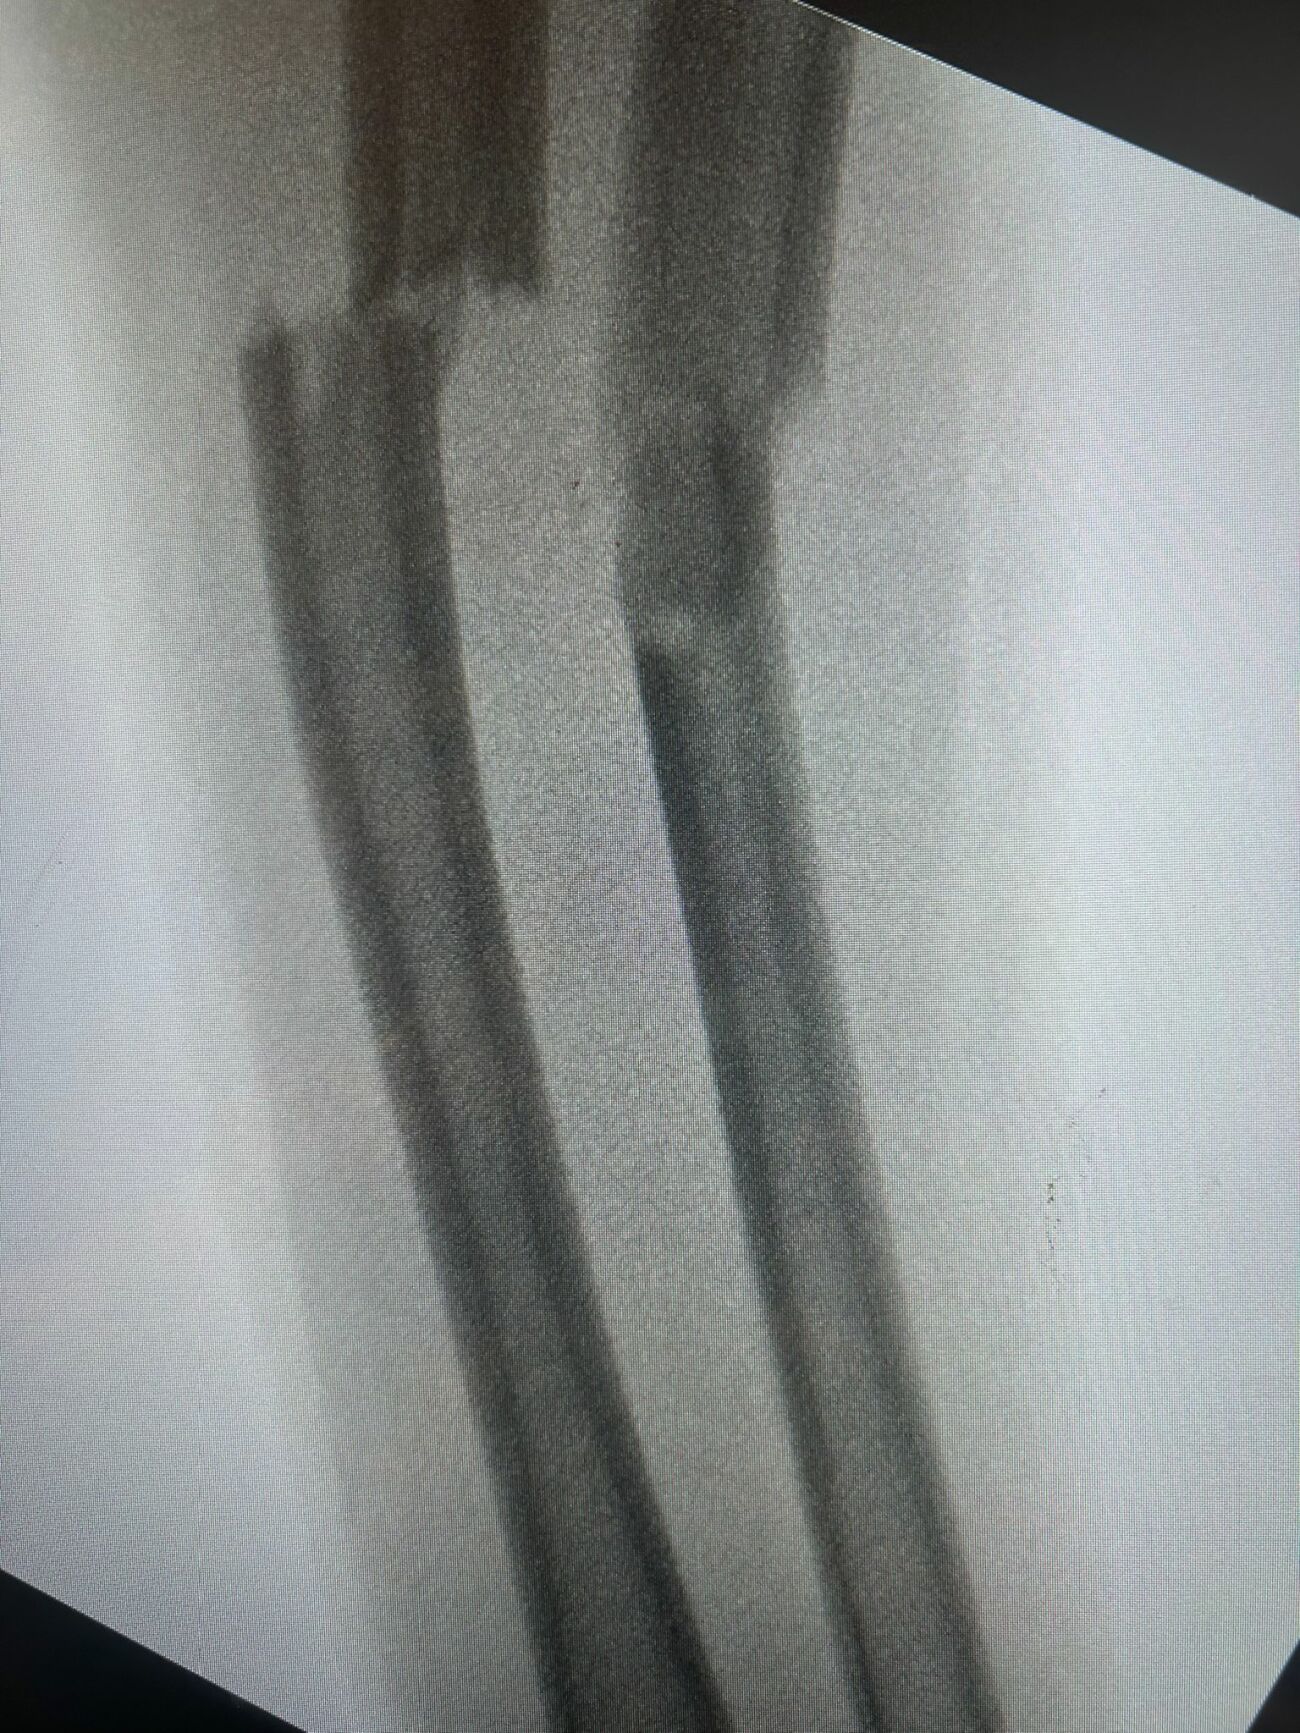

"הילדה סובלת משבר באמה, עברה גיבוס זמני במלר"ד הילדים, ותתאשפז לצורך קיבוע שיתבצע בחדר ניתוח. בפתחו של הקיץ והחופש הגדול, אנחנו כבר עכשיו רואים עליה בפציעות של ילדים. רק בשבועיים האחרונים ראינו מספר ילדים עם חתכים כתוצאה מקפיצה בטרמפולינה. חשוב מאוד להשגיח על הילדים בכל זמן, וגם במקומות שנראים בטוחים. אין לקפוץ על טרמפולינות מתחת לגיל שש ולא בזוגות, ואפילו רצוי להימנע ככל הניתן. זו ההזדמנות להזכיר שגם סכנת הטביעות גוברת בתקופה זו, בעיקר בבריכות ביתיות ומקורות מים, גם נמוכים. אנחנו מבקשים מההורים להיות בתשומת לב מלאה, ככל הניתן".